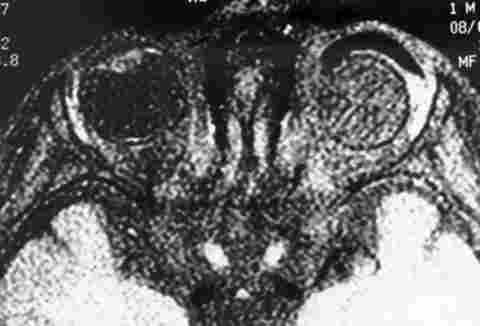

RNM, IMÁGENES EN T1 CON SUPRESIÓN GRASA TRAS ADMINISTRACIÓN DE Gd-DPTA. CAPTACIÓN LLAMATIVA DE CONTRASTE EN LA TOTALIDAD DEL IMPLANTE.